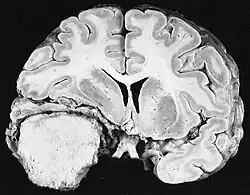

Ionizing radiation

Sources of ionizing radiation include medical imaging, and radon gas. Ionizing radiation is not a particularly strong mutagen.[87] Medical use of ionizing radiation is a growing source of radiation-induced cancers. Ionizing radiation may be used to treat other cancers, but this may, in some cases, induce a second form of cancer.[87] Radiation can cause cancer in most parts of the body, in all animals, and at any age, although radiation-induced solid tumors usually take 10–15 years, and can take up to 40 years, to become clinically manifest, and radiation-induced leukemias typically require 2–10 years to appear.[87] Radiation-induced meningiomas are an uncommon complication of cranial irradiation.[92] Some people, such as those with nevoid basal cell carcinoma syndrome or retinoblastoma, are more susceptible than average to developing cancer from radiation exposure.[87] Children and adolescents are twice as likely to develop radiation-induced leukemia as adults; radiation exposure before birth has ten times the effect.[87]

Ionizing radiation is also used in some kinds of medical imaging. In industrialized countries, medical imaging contributes almost as much radiation dose to the public as natural background radiation. Nuclear medicine techniques involve the injection of radioactive pharmaceuticals directly into the bloodstream. Radiotherapy deliberately deliver high doses of radiation to tumors and surrounding tissues as a form of disease treatment. It is estimated that 0.4% of cancers in 2007 in the United States are due to CTs performed in the past and that this may increase to as high as 1.5–2% with rates of CT usage during this same time period.[93]

Residential exposure to radon gas has similar cancer risks as passive smoking.[87] Low-dose exposures, such as living near a nuclear power plant, are generally believed to have no or very little effect on cancer development.[87] Radiation is a more potent source of cancer when it is combined with other cancer-causing agents, such as radon gas exposure plus smoking tobacco.[87]